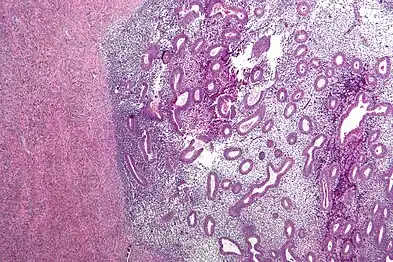

Histopathology

For a histopathological diagnosis, at least two of the following three criteria should be present:[88]

Immunohistochemistry has been found to be useful in diagnosing endometriosis as stromal cells have a peculiar surface antigen, CD10, thus allowing the pathologist go straight to a staining area and hence confirm the presence of stromal cells and sometimes glandular tissue is thus identified that was missed on routine H&E staining.[89]